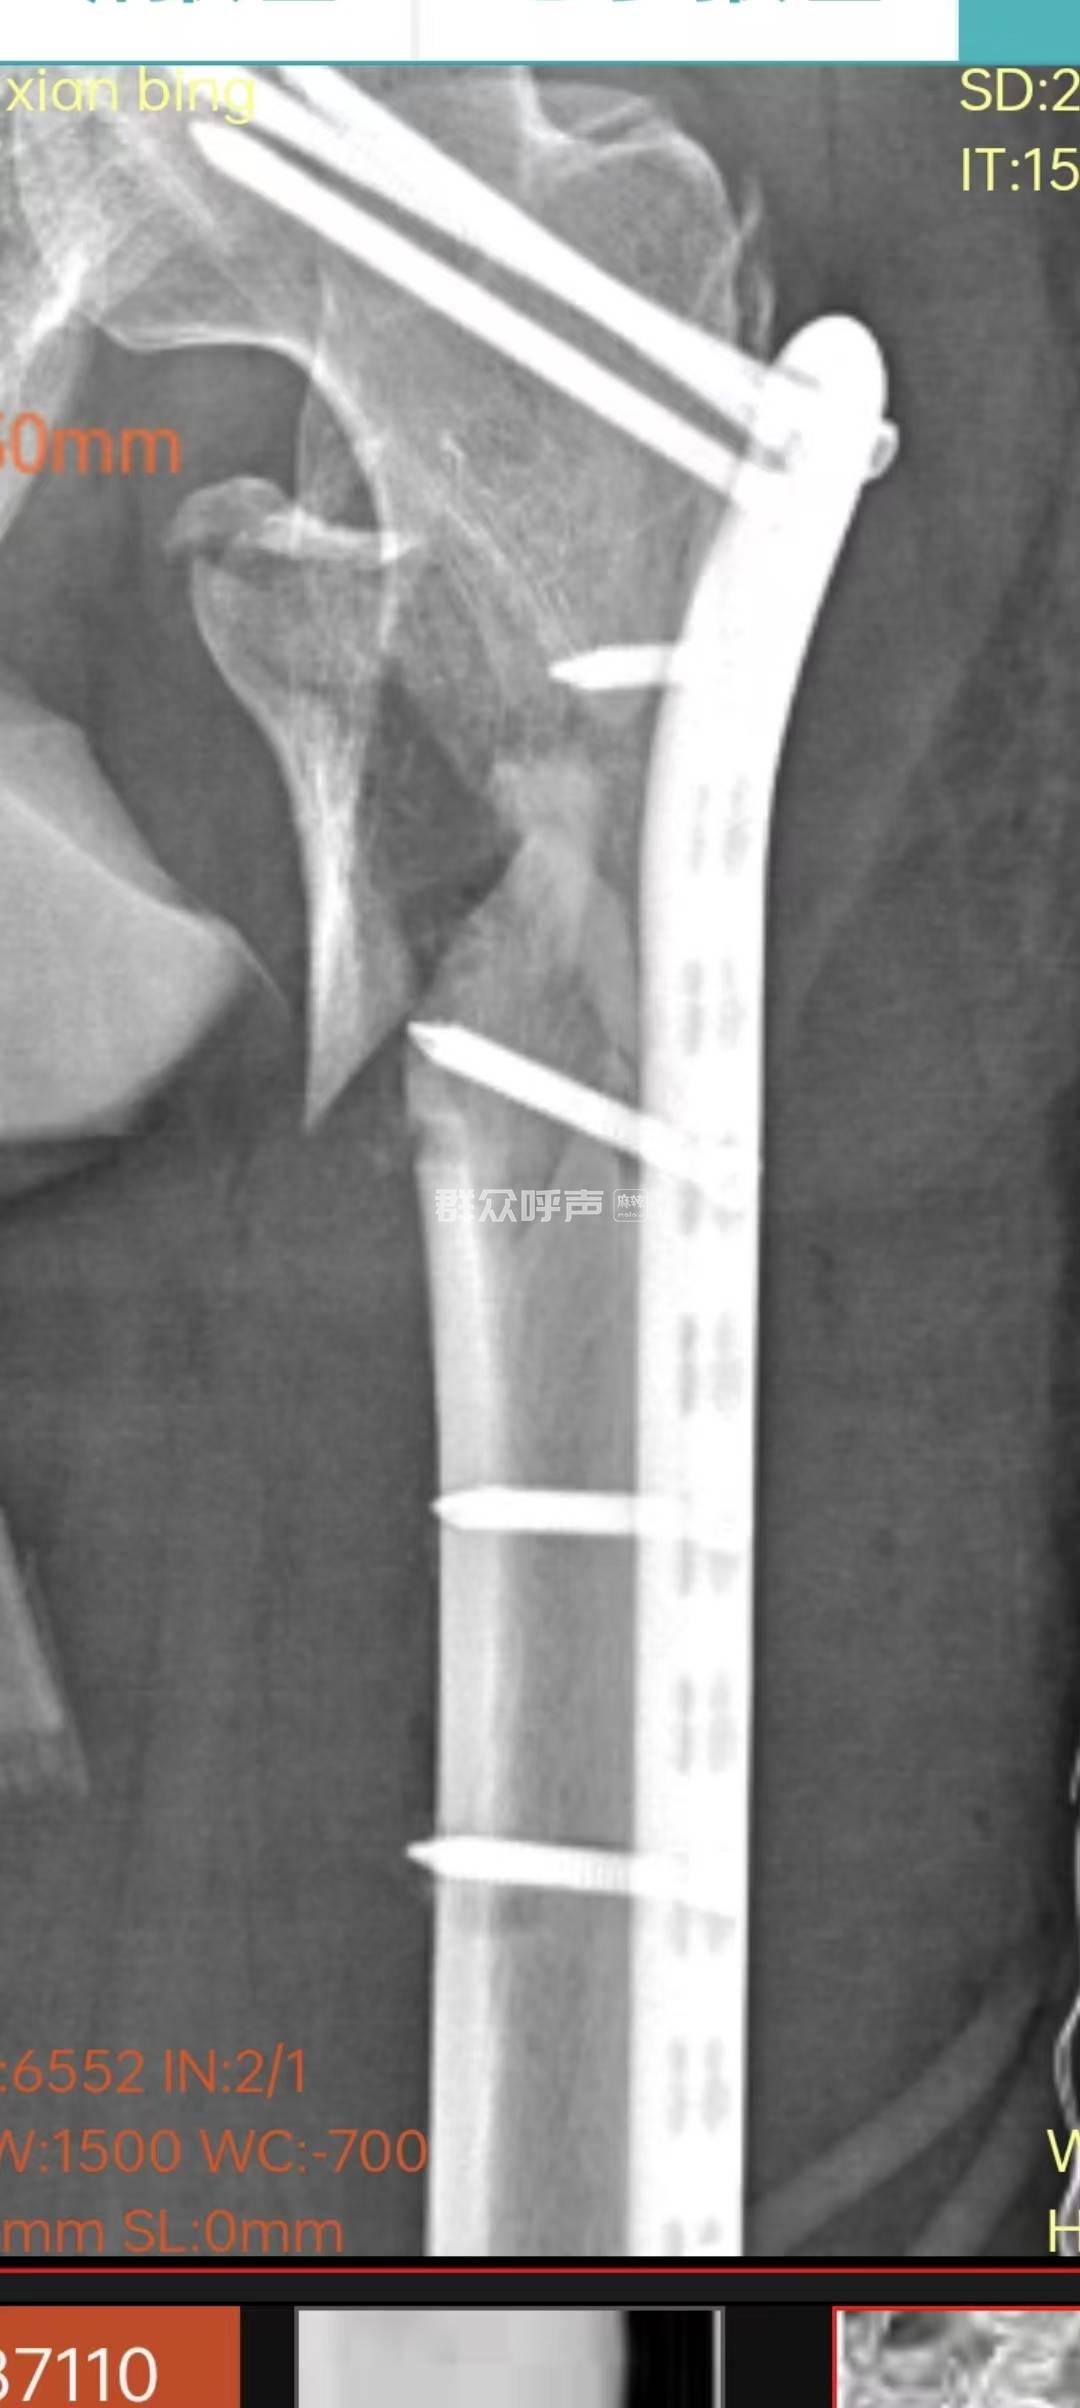

[投诉] 四川省卫生健康委员会投诉信